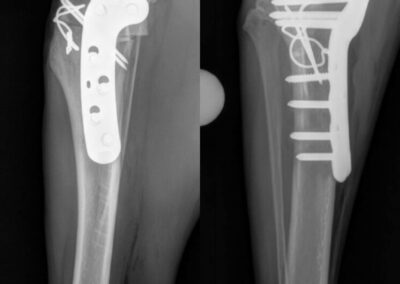

Fracture Repair

We provide surgical fracture repair for many types of broken bones. Treatment plans are individualized based on the location and complexity of the fracture, your pet’s age and size, and overall health.

Large Dog Radius Fracture Before

Large Dog Radius Fracture After #1

Large Dog Radius Fracture After #2